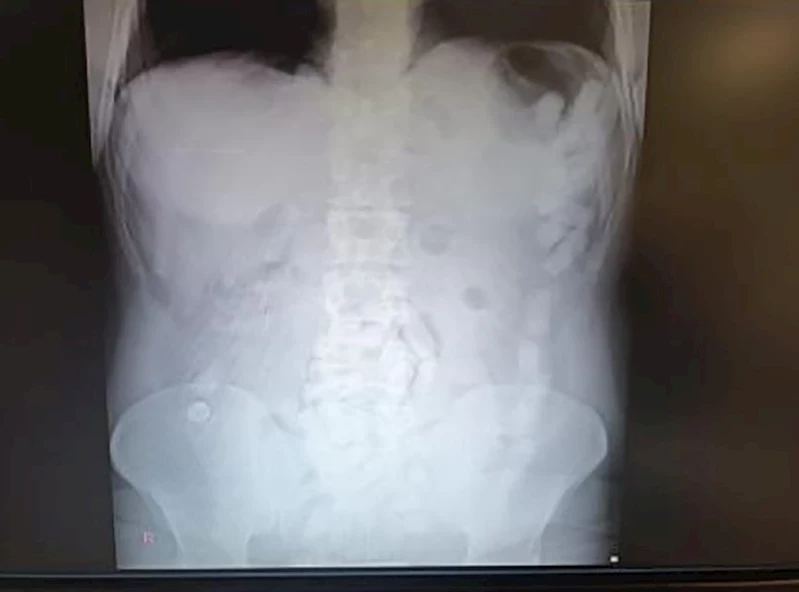

4 Mayıs 2024’te Kayseri İl Emniyet Müdürlüğü Narkotik Suçlarla Mücadele Şube Müdürlüğü ekipleri, yabancı uyruklu A.H.’nin ülkeye giriş yaparak üzerindeki uyuşturucu maddeleri Kayseri’ye getireceğini tespit etti. Şahsı takibe alan ekipler, yerini tespit ettikten sonra operasyon düzenledi. Kayseri Şehir Hastanesinde ultrason çekimi ile yapılan kontrolde şahsın midesinde çok sayıda kapsül olduğu tespit edildi. Yapılan operasyonla şahsın midesinden çıkarılan 100 adet kapsülün içerisinde 729 gram uyuşturucu madde ele geçirildi. İşlemlerinin ardından adliyeye sevk edilen şüpheli, çıkarıldığı mahkemece tutuklanarak cezaevine gönderildi.